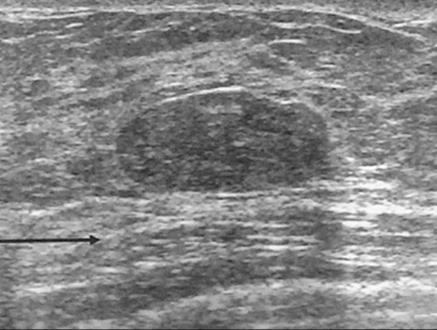

17. The mass in Fig. 10–20 can best be described as:

(A) irregular

(B) circumscribed

(C) macrolobulated

(D) spiculated

FIGURE 10–20.